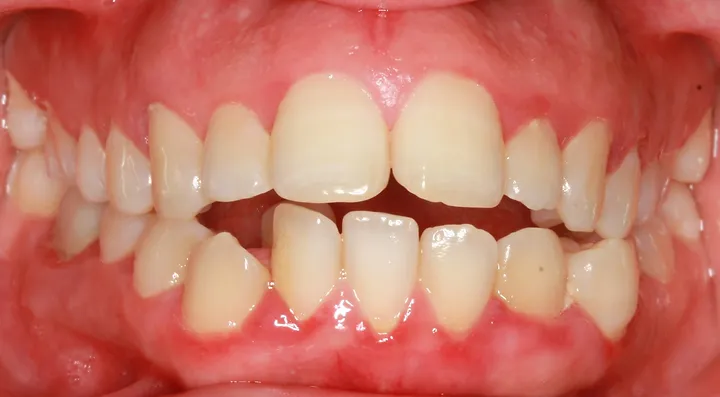

87f545_bc43680091984bbdb74de17eb337bbfd~mv2_d_1920_1280_s_2.webp

87f545_f42d29ecf80a4b9fa8b3f13471579528~mv2_d_1920_1280_s_2.webp

87f545_1c85956a5c2243d1acfc7176f18e69a7~mv2_d_1920_1280_s_2.webp

87f545_91b464f1d91749a39ae126d3341b6d30~mv2.webp

look how the maxilla was ripped apart on this one holy chit